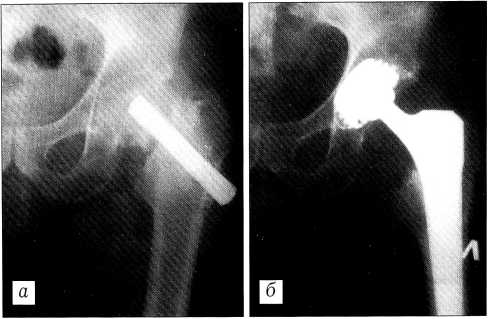

Эндопротез используется при деформирующем коксартрозе, асептическом некрозе головки бедренной кости, диспластическом коксартрозе, ревматоидном артрите, ложных суставах шейки бедренной кости, медиальных переломах шейки бедра у пожилых людей, болезни Гаше, красной волчанке и других заболеваниях тазобедренного сустава (рис. 5). Операции выполняются из наружного доступа по общепринятой методике и включают следующие этапы: разрез кожи и подкожной клетчатки, рассечение мышц, капсулы, резекцию головки, подготовку вертлужной впадины, установку чашки эндопротеза, подготовку бедренного канала с помощью рашпилей, установку ножки и головки эндопротеза, вправление их в вертлужный компонент протеза, дренирование сустава, при необходимости дренирование подкожной клетчатки и мышц, шов мягких тканей. Необходимо применение антибиотиков накануне операции, во время ее проведения и в послеоперационном периоде.

Рис. 5. Рентгенограммы больного с ложным суставом шейки бедра: а — до, б — после эндопротезирования.

С 1996 по 2000 г. в специализированных ортопедо-травматологических отделениях Республики Беларусь имплантировано более 600 эндопротезов нашей конструкции. В клинике травматологии и ортопедии Белорусского института усовершенствования врачей за 1997-1999 гг. произведено 173 операции эндопротезирования. Во время операции и ближайшем послеоперационном периоде имели место следующие осложнения: вывих головки протеза (5 случаев), парез седалищного (2) и бедренного (2) нервов, повреждение сосудов (2), глубокое нагноение раны (3).